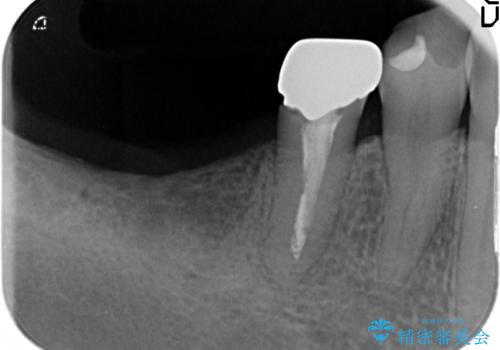

インプラント治療による咬合機能回復

- 失ってしまった奥歯の咬合機能の回復を求めて来院されました。

骨の幅が十分にないのでインプラント治療に伴い、人工骨の造成を同時に計画します。

インプラントは高い確率で骨に結合し、しっかりとした咬合力を回復することができます。

長年安心してしっかりと噛んでいただけるよう今回は骨を増成する治療計画としました。